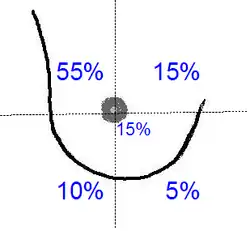

Linke Brust häufiger als rechte Brust

Statistisch gesehen ist die linke Brust, sowohl bei Frauen als auch Männern, häufiger von Brustkrebs betroffen als die rechte.[49] Davon sind alle Populationen betroffen.[50] Mit zunehmendem Alter wird der Unterschied noch größer.[51] Diese für die linke Brust erhöhte Rate trifft offensichtlich nicht für Tumoren zu, die ihren Entstehungsort im oberen äußeren Quadranten haben.[52] Die Wahrscheinlichkeit, dass die linke Brust an Krebs erkrankt, ist – je nach Studie – um fünf bis sieben Prozent höher als bei der rechten.[49] Bei Männern liegt dieser Wert sogar bei zehn Prozent.[53]

Die Ursachen für dieses Phänomen sind noch weitgehend unklar.[54] Diskutiert werden unter anderem Schlafgewohnheiten,[55] Händigkeit,[44][56] Unterschiede in der Brustgröße und den Gehirnstrukturen sowie Präferenzen beim Stillen.[55] Eine andere Hypothese sieht in der embryonalen Entwicklung des auf der linken Körperseite befindlichen Herzens eine mögliche Ursache.[57]

Bei anderen Organen, wie beispielsweise der Lunge und den Hoden, ist eine ähnliche statistische Häufung zu beobachten. Bei diesen beiden Organen ist die Wahrscheinlichkeit, dass die rechte Hälfte des Organs betroffen ist, um 13 % höher. In diesen Fällen erklärt man sich diesen Unterschied durch das meist kleinere Gewebevolumen der linken Organhälfte.[49]